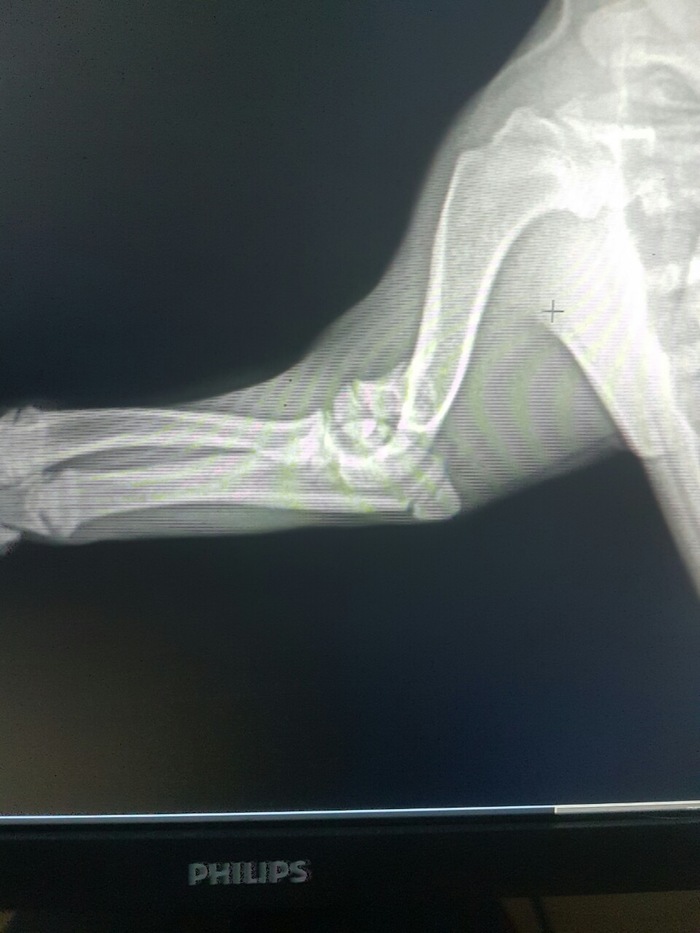

Нужна помощь ветеринара...

Просто слезно умоляю ветеринаров помочь.

Наша прекрасная Буля сломала лапку... это случилось пару часов назад и я до сих пор в шоке.. 😭

Ветеринар сказал, что нужна операция, но хочется быть уверенными, что это действительно необходимо.

Пожалуйста, если есть на просторах Пикабу ветеринары, скажите, на сколько все серьёзно?